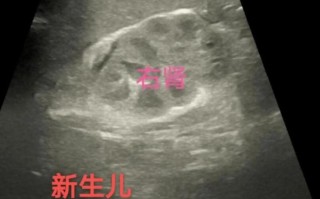

新生儿健康护理 新生儿肾上腺皮质增生有哪些典型症状? 新生儿肾上腺皮质增生症,简称CAH,是一组由于肾上腺皮质激素合成过程中所需酶的缺陷所引起的遗传性疾病,这个缺陷导致身体无法正常合成皮质醇和/或醛固酮,而一些中间产物(如雄激素)则会异常增多,根据缺乏酶... 99ANYc3cd6 2025-12-04 1 #新生儿肾上腺皮质增生症状表现 #新生儿肾上腺皮质增生典型特征 #新生儿肾上腺皮质增生早期症状